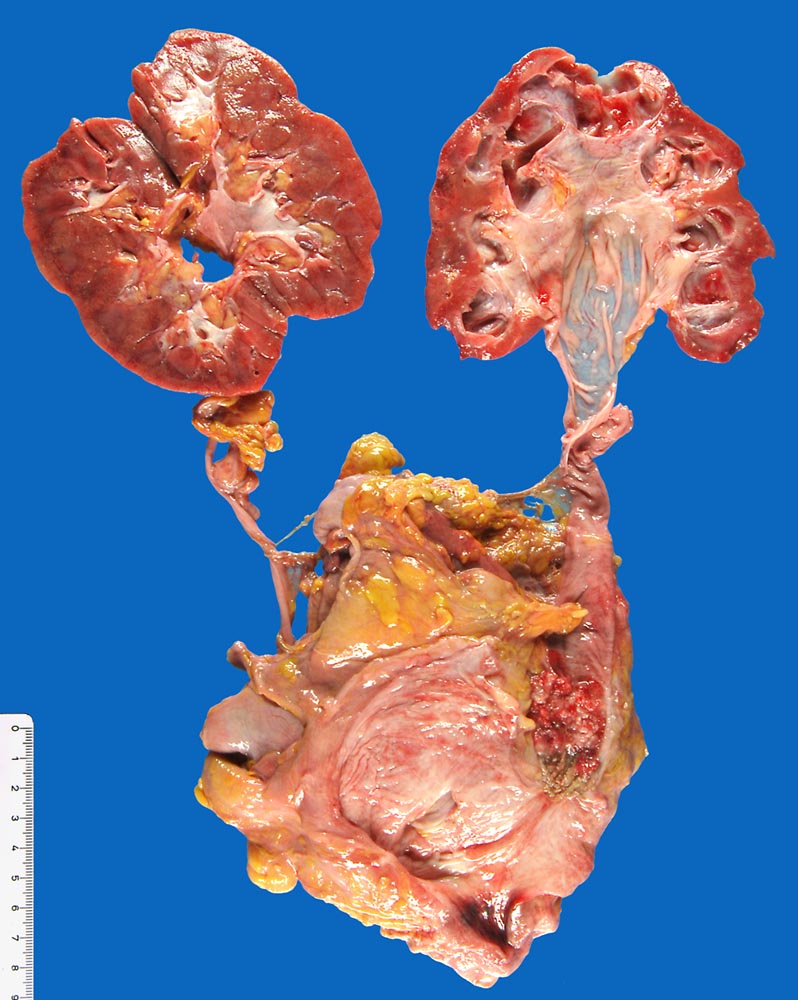

Invasives papilläres Urothelkarzinom mit Hydronephrose

Papillärer Tumor im distalen Ureter. Distal davon Richtung Harnblase ist der granulierende Ulkusgrund der transurethralen Resektion vor 4 Monaten sichtbar. Hydronephrose und Hydroureter auf der Seite des ureteralen Tumors.

Aktuell: Reste des wenig differenzierten Urothelkarzinoms im distalen Ureter. Ausdehnung: 10mm, rpT2a G3 pN2 M1 L1 V1.

Transurethrale Resektion eines wenig differenzierten papillären Urothelkarzinoms vor 1 Jahr pT1. Resektion eines Rezidivs des Karzinoms vor 4 Monaten.